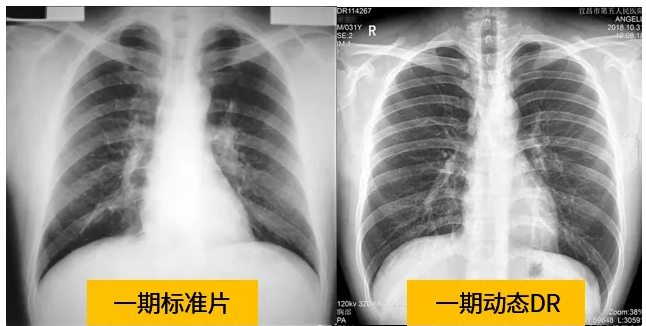

動態(tài)dr的拍攝效果圖

動態(tài)DR技術(shù)與普通DR單截面診斷的不同就是在操作過程中,可以隨時切換成透視模式,透視/攝片模式實時切換,對陰影進(jìn)行多角度動態(tài)的鑒別。實時點片、實時回放、連續(xù)點片等多功能大大的增加了初診的準(zhǔn)確率。在小陰影的形態(tài)和性質(zhì),特別是不規(guī)則小陰影的判斷方面提升,從而達(dá)到提高胸片整體判斷準(zhǔn)確性。

根據(jù)數(shù)據(jù)統(tǒng)計表現(xiàn),利用動態(tài)dr進(jìn)行檢查的話,圖像的質(zhì)量和輻射劑量相對較少。并且動態(tài)DR在圖像清晰度和射線穿透力方面完全能達(dá)到塵肺診斷的要求。這種檢查效果的精準(zhǔn)和便捷性是和普通設(shè)備不一樣的,動態(tài)DR塵肺攝影應(yīng)用于塵肺疾病診斷中,可以提高檢出率及優(yōu)片率。